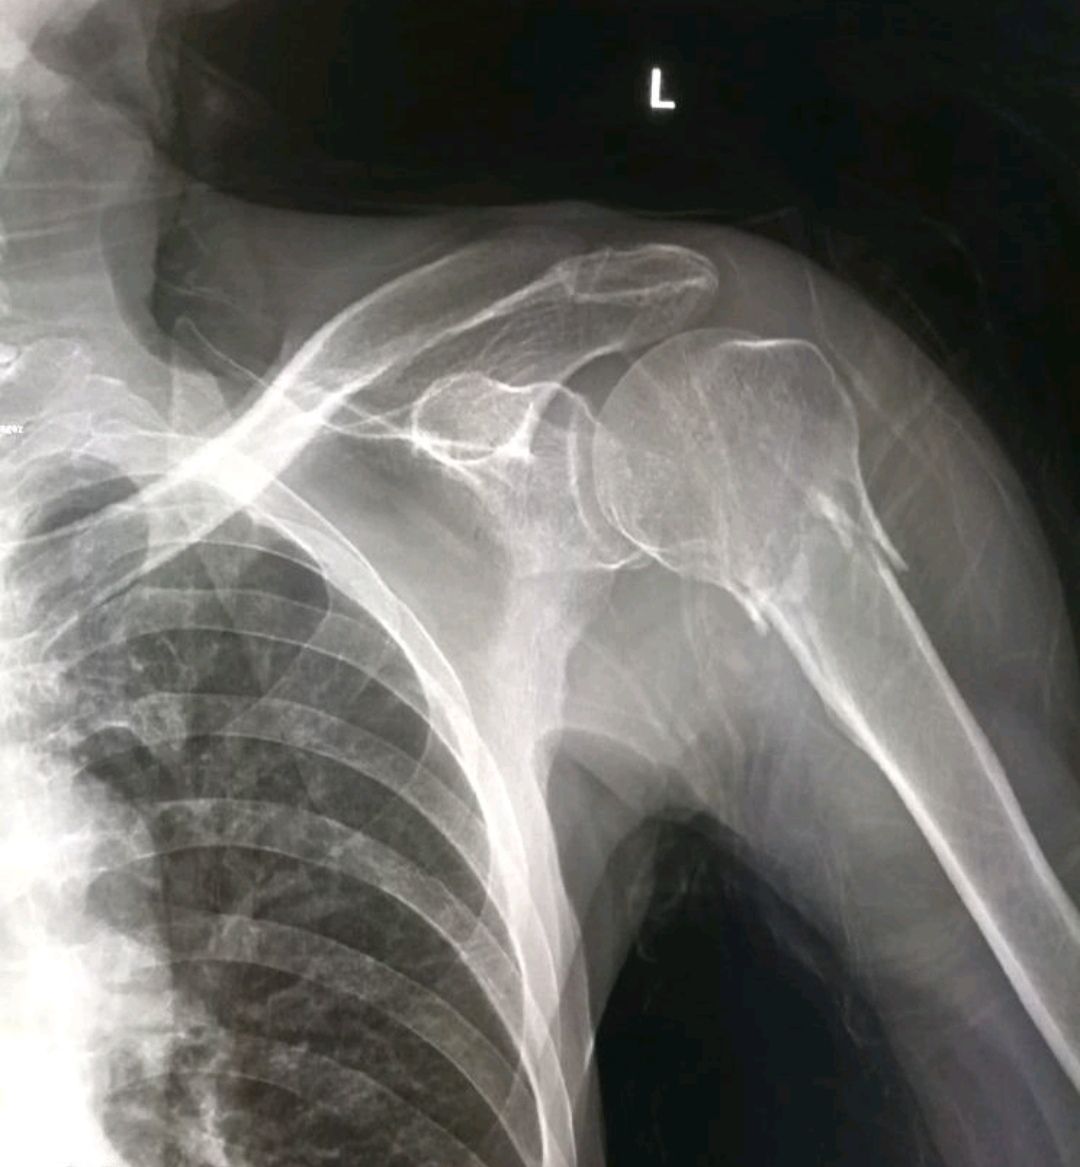

患者于4小时前在地边干活时发生晕厥,从约1米高的塄坎上摔下,左侧身倒地,倒地后即感左侧肩关节,左侧肩关节活动受限。伤后未行特殊处理,用出租车急送我院就诊。门诊拍片后以“左肱骨外科颈骨折”之诊断收住院。

查体:左侧肩关节局部明显肿胀,局部皮肤无青紫瘀斑,无方肩畸形,左侧肱骨近端压痛剧烈,可触及骨摩擦感,左侧肩关节活动受限,杜加氏症阴性,左上肢末梢血运及感觉正常。

X线:左侧肱骨外科颈骨折。

诊断:左侧肱骨外科颈骨折。

治疗:左侧肱骨外科颈骨折切开复位解剖钢板内固定术。